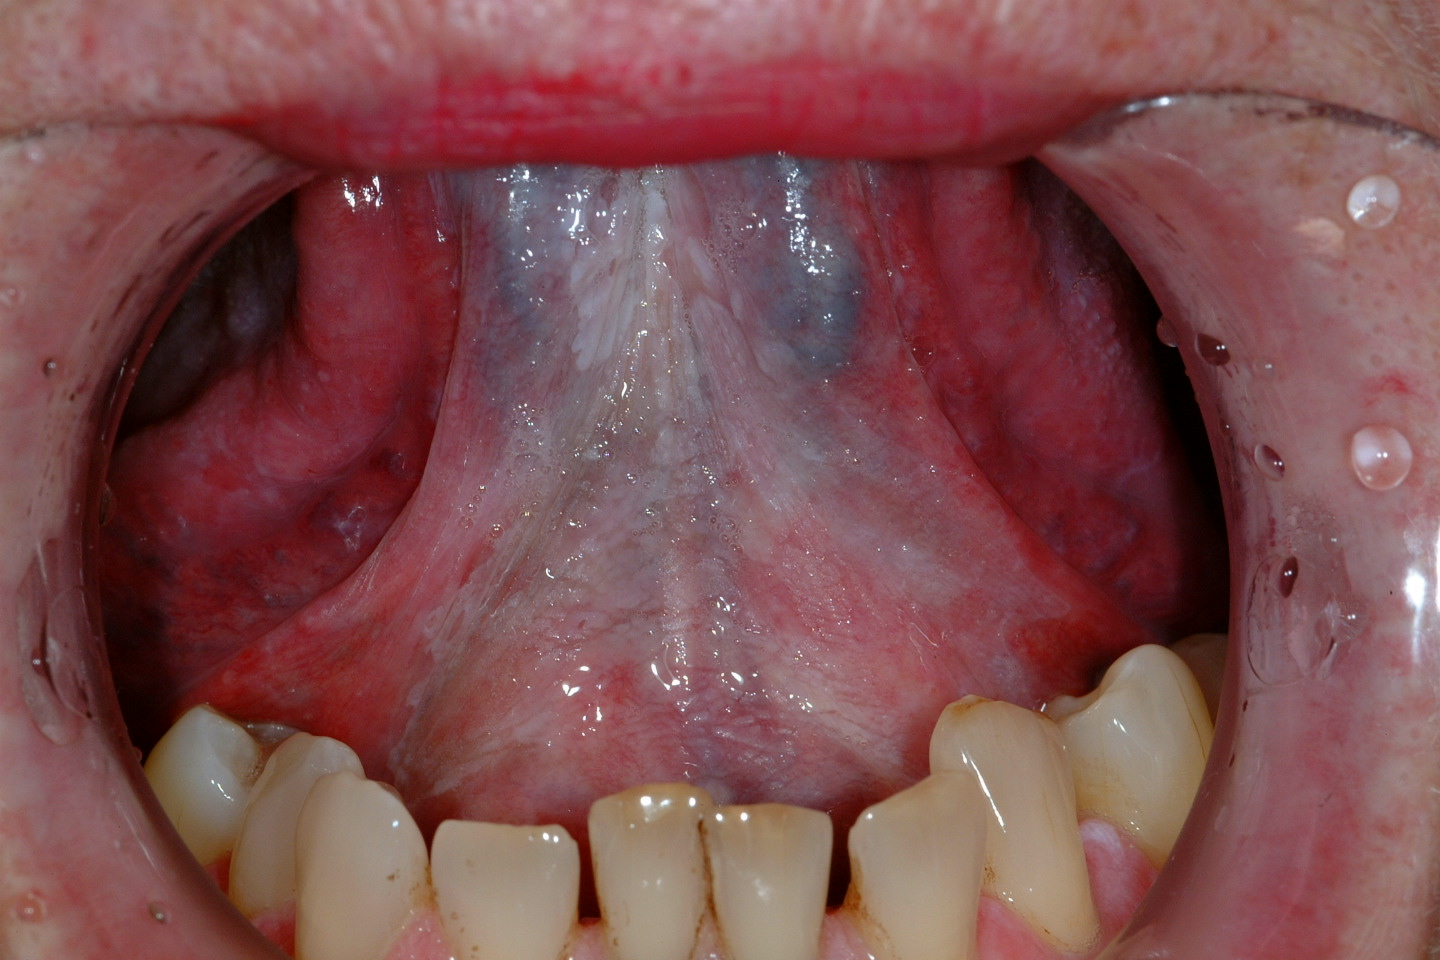

Lichen planus

Lichen planus is a chronic autoimmune disorder of the skin and often affects the oral mucosa as well. It usually shows characteristic streaks or strands of white keratosis (see Figure 5). Lichen planus is sometimes associated with epithelial dysplasia, a so called lichenoid dysplasia. Of the fairly low malignant transformation risk (the incidence is approximately 1 to 3 %), the majority of cases is due to lichenoid dysplasia. It is important to note that the real risk of transformation of lichenoid dysplasia and erosive lichen planus warrants intervention whereas reticular pattern lichen planus that is symptomless doesn’t need anything in the way of intervention. This is fortunate given how common that condition is.